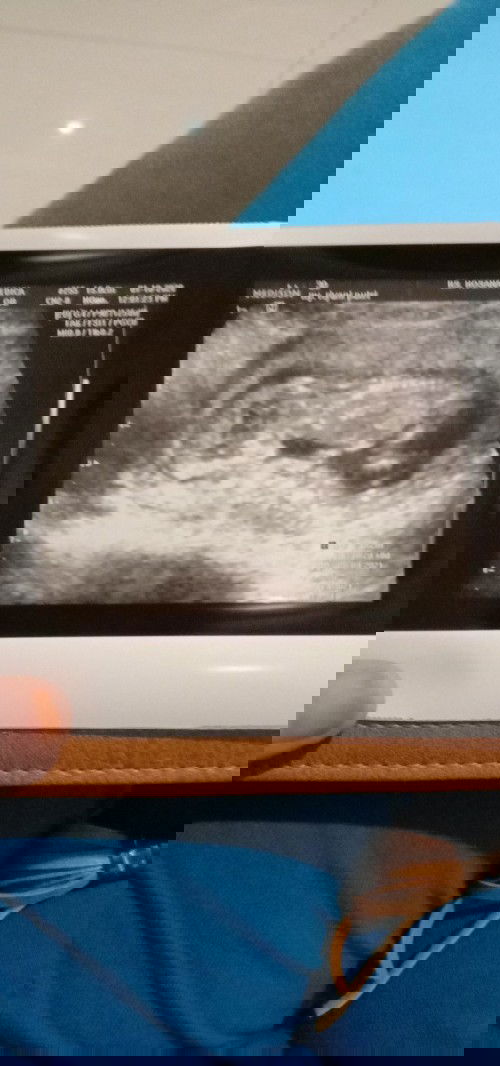

Sedikit cerita ya bun dulu dibulan januari tahun ini sempet pernah isi tapi allah berkehendak lain 😊 ada masalah pendarahan ternyata gak bisa dipertahankan janin nya aku sempet sedih 🥺 yg lebih sedih nya pas setelah semua nya bersih dicek lagi sama dokter yg sudah sabar nanganin aku ternyata malah ada kista makin dwon dan makin kejer nangis gak berhenti" ☹️ sampe berpikir aku bisa gak ya punya anak sedangkan suamiku ingin bgt punya anak ☹️, makin kesini makin coba buat tenang dan nyari" solusi biar bisa hamil.. Aku nyoba buat program hamil pakai madu yg nemu dri iklan fb aku asal pencet" aja ternyata program nya bisa suami istri akhirnya coba untuk beli dengan ikhtiar ku dan suami.. Ditambah aku konsumsi folavit sehari 1x dan dibulan juli aku udh telat haid tapi untuk nyoba tespek di bulan agustus dan ternyata allah menjawab semua nya 😇 aku dan suami masih dikasih kepercayaan sama allah 😇 pas tau positif aku gak berani buat usg nunggu sampe si janin besar aja dulu.. Dan pas tgl 1 bulan oktober ini aku coba beraniin diri untuk usg sama suami 😊 pas di usg ma syaa allah aku netesin air mata karena pas di usg anakku gerak" gak bisa diem 🥺😊 suamiku pun netes air mata karena seneng lihat anak nya sudah berbentuk utuh 😊 pas ke print anakku lagi tengkurep 😇 alhamdulillah allah maha melihat, maha segala nya dan segala nya milik allah buat kalian yg blm dikasih jangan putus asa ya 😇 terus berjuang dan ikhtiar agar allah mengqobulkan doa kalian satu kunci dri saya tetap semangat jangan menyerah 😇😇😇😇😇#jangandibully